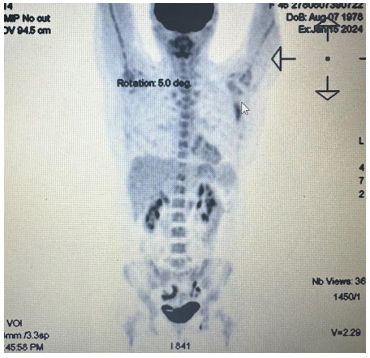

In March 2024, FDG PET/CT showed no residual active metabolic damage and a favorable response to oncological treatment (Figure 8).

Figure 8: PET/CT showing no residual active metabolic damage